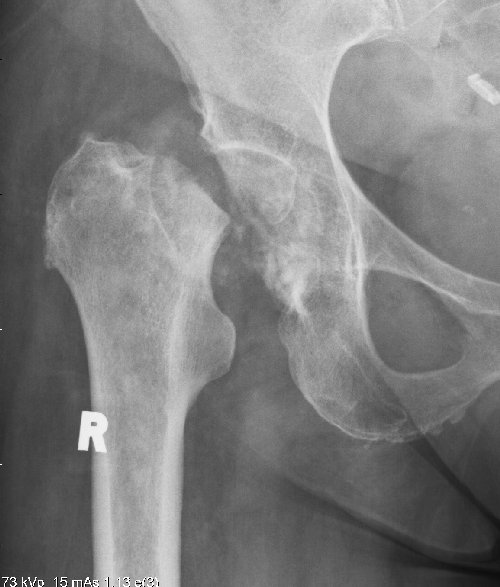

Avascular Necrosis

This is a condition caused by a failure of the blood supply to a part, or the whole, of the femoral head. As the bone is exposed to daily trauma it cannot regenerate and may start to collapse. The extent of the collapse is variable, healing will solidify the head but may lead to a mis-shapen head and therefore early osteoarthritis.

In extreme cases the whole femoral head may fragment and the bone dissolves away.

27/05/2011 - Not operated upon!